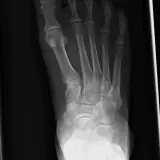

MSK Radiographs